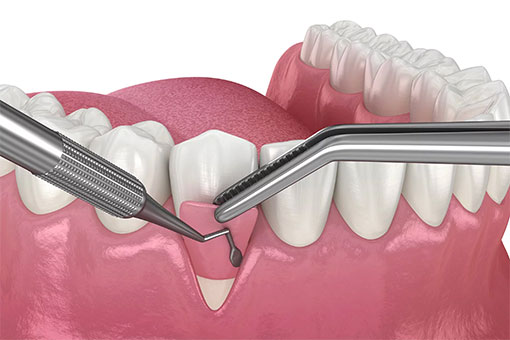

歯周ポケット検査

歯と歯ぐきの間にある歯周ポケットの深さを測り、歯ぐきの炎症や歯周病の進み具合を確認する検査です。痛みはほとんどなく、短時間で終わるため、お子さまから大人まで安心して受けられます。

測定結果をもとに、どの歯に重点的なケアが必要かを確認できます。